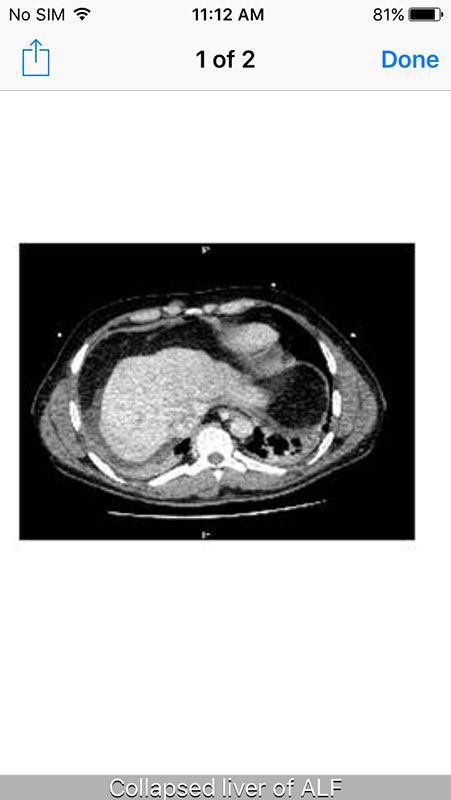

Information is presented in a textual format in a concise manner and it is supported by illustrations and images (for example, the radiology or histology findings in Diagnosis), as well as the tables and charts.